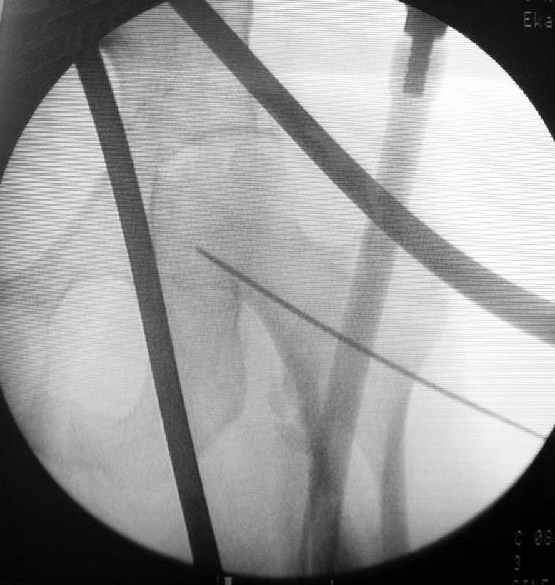

Наш туземный подход - flat radiolucent table и спицевой дистрактор.

DK> Чтобы не расколоть чрезвертельный перелом провели временную спицу

DK> ближе к переднему кортексу,

Мы обычно проводим спицу ближе к заднему кортексу - иногда бывает, гвоздь смещается кзади, за фрагменты, особено при многооскольчатых переломах...